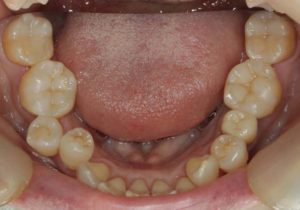

どのように変わったか、下の写真をご覧ください。

銀歯が多かったのですべて昔の銀歯の下もちりょうしながらセラミックにかえることができてとても満足しています。やっぱり白い歯よいですね。

治療お疲れ様でした。たくさん銀歯が入っていたのですが、最後には真っ白になりましたね。銀歯をやり直す材料にはセラミックとプラスティックがあるのですが、基本的にできるだけプラスティックで治すようにしています。この患者さんも、可能な限りプラスティックで治し、どうしても無理なところだけセラミックにしました。そのため歯を削る量が少ないことに加え、費用もかなり抑えることができます。たくさん治しましたが、全部セラミックで治さなければならないとなっていたら、もっともっと時間も費用もかかっていたかもしれません。当院では、初診時に治療方針や期間や費用などを1時間ほどかけて詳しく説明していますので、患者さんには治療内容について十分納得していただいていると考えています。「親身になって治療してくれる」とおっしゃっていただいたことは、そういったところを評価して頂いたのではいかと思っております。